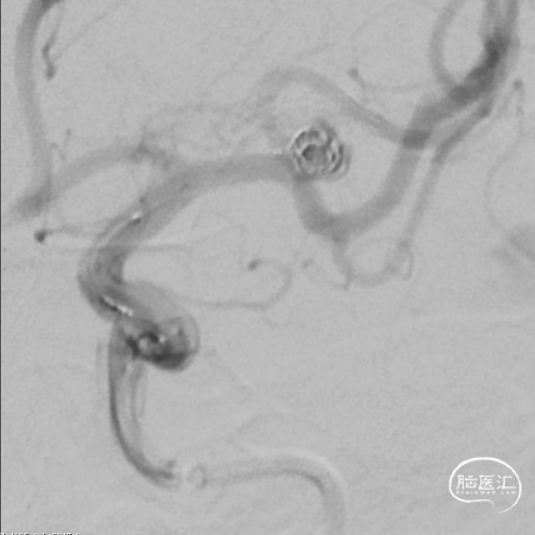

引入8F 导引导管及6F 中间导管至左侧颈内动脉,接加压管肝素盐水(500ml盐水2000单位肝素)4路;200cm Synchro-14微导丝配合SL-10微导管超选进入左侧大脑中动脉M1段上干备用(大脑中动脉M1段上干与动脉瘤瘤颈关系密切);200cm Synchro-14 微导丝配合Echelon-10微导管超选进入瘤体内,沿微导管填入Target 3mm×10cm 3D弹簧圈一枚成篮良好;后经SL-10微导管送入Atlas 3.0mm×24mm支架直至支架中部位于瘤颈处,缓慢释放支架,释放支架时通过半释放状态在瘤颈部小心推压将支架形成“穹窿”,穹顶部分支架可疝入瘤颈处,将宽颈动脉瘤变为窄颈。造影示支架稳定、帖壁良好;继续沿微导管行动脉瘤内弹簧圈栓塞术,先后放入2mm×6cm(两枚)、2mm×4cm、2mm×4cm、1.5mm×2cm弹簧圈共6枚;

释放支架前经导引导管缓慢注入替罗非班6ml,之后持续静脉泵入,速度5ml/h。手术历时60分钟,麻醉顺利苏醒,神经系统查体:未见阳性体征。NIHSS评分:0分;Raymond分级:Ⅰ级,mRS评分:0分。术后即刻行C-arm CT头颅扫描,未见出血,动脉瘤填塞致密,支架开放良好。